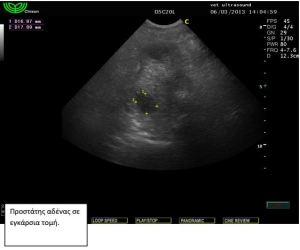

ραχιαία. Ο προστάτης ήταν διογκωμένος με παρουσία μεγάλων

κύστεων στο παρέγχυμά του. Τα υποσφυικά λεμφογάγγλια ήταν